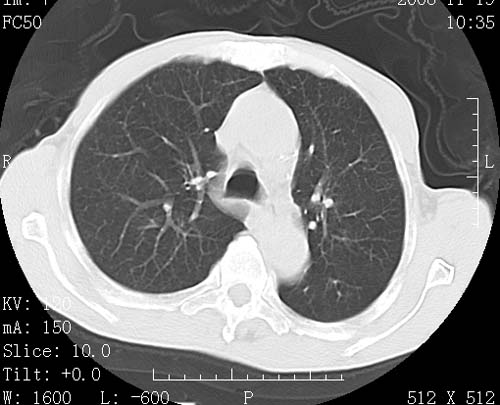

术前查体,双肺部结节是转移?结核?请点评

转移 隆突下淋巴结亦肿大

首先考虑转移,纵隔内淋巴结亦肿大;

1)符合食管癌表现。2)两肺及纵隔淋巴结多发性转移瘤。3)左肺上叶舌段及两肺下叶炎症感染。

食管癌伴双肺转移,评述:肺部毛细血管网丰富,全身血液均快速流经肺部,癌细胞容易过滤定植,形成转移瘤,影象特点为以毛细血管末梢为中心的结节灶,边缘光滑锐利,少见有中心空洞着,不同来源的转移瘤可有各自特点,如甲状腺癌为双肺弥漫性微结节,本例有原发灶,双肺影象灶典型,左肺舌段条带状网格样伴胸膜天幕征,可视为癌性淋巴管炎。